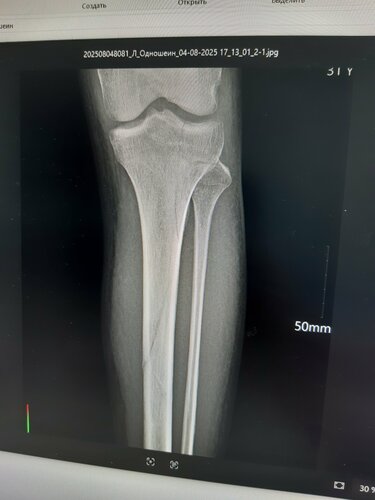

Добрый день. Припереломе Большой берцовой кости, максимум что смогла сделать эта больница это откочать кровь из сустава и наложить гипс. Снимков они не предоставили, как бы я не умолял (говорили нам некогда тебе анотомию преподавать, ты там всёравно ничего не поймёшь). В итоге после снятия гибса у этих же "врачей", разумеется опять без предоставления снимков на руки ( показали только на собственном телефоне), не давая никокого заключения сказали можешь идти от перелома и следа не осталось, как в дальнейшем выесниться они даже не в том месте снимок сделали. Через неделю я начал беспокоиться что не могу согнуть ногу и обратился в клиннику "Шанс", где мне сделали снимок, скинули его на диск, всё "разжували", чтобы я понял, и оказалось мне и гипс то рано сняли и на ногу вообще ещё рано втавать, а в 14 - й больнице сказали всё зажило можеш полностью вставать но ногу. Что касается общения с больными, судите сами. В первый день обращения, мне стали откачивать кровь из колена (я им только за это блогадарен сделали всё хорошо), но так как у меня вес тела всего 52 кг, а крови откачали много 100 мл.(относительно моего веса), мне сделалось плохо, в глазах потемнело и в этот момент они меня стали прогонять (давай быстрее у нас времени мало), я лежал не уходил (да и не смог бы если бы даже захотел, у меня нижняя половина туловища почемуто отказала полностью), они снапором меня стали прогонять, в это время я стал писать другу по ватсапу , который меня ждал в коридоре, с просьбой заступиться за меня, славо богу успел написать, потомучто у меня стали отбирать телефон (прямо силой из рук вырывать), когда друг зашёл они успокоились. На фотографиях видно с каким переломом меня выпустили из 14 -й больници и сказали что от перелома и следа не осталось, можеш идти.